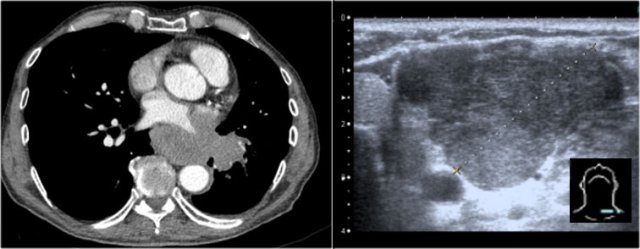

Pericardial effusion

Whenever we encounter a large heart figure, we should always be aware of the possibility of pericardial effusion simulating a large heart.

On the chest x-ray it looks as if this patient has a dilated heart while on the CT it is clear, that it is the pericardial effusion that is responsible for the enlarged heart figure.

Especially in patients who had recent cardiac surgery an enlargement of the heart figure can indicate pericardial bleeding.

This patient had a change in the heart configuration and pericardial bleeding was suspected.

Ultrasound demonstrated only a minimal pericardial effusion.

Continue with the CT.

There is a large pericardial effusion, which is located posteriorly to the left ventricle (blue arrow).

The left ventricle id filled with contrast and is compressed (red arrow).

At surgery a large hematoma in the posterior part of the pericardium was found.

Notice that on the anterior side there is only a minimal collection of pericardial fluid, which explains why the ultrasound examination underestimated the amount of pericardial fluid.